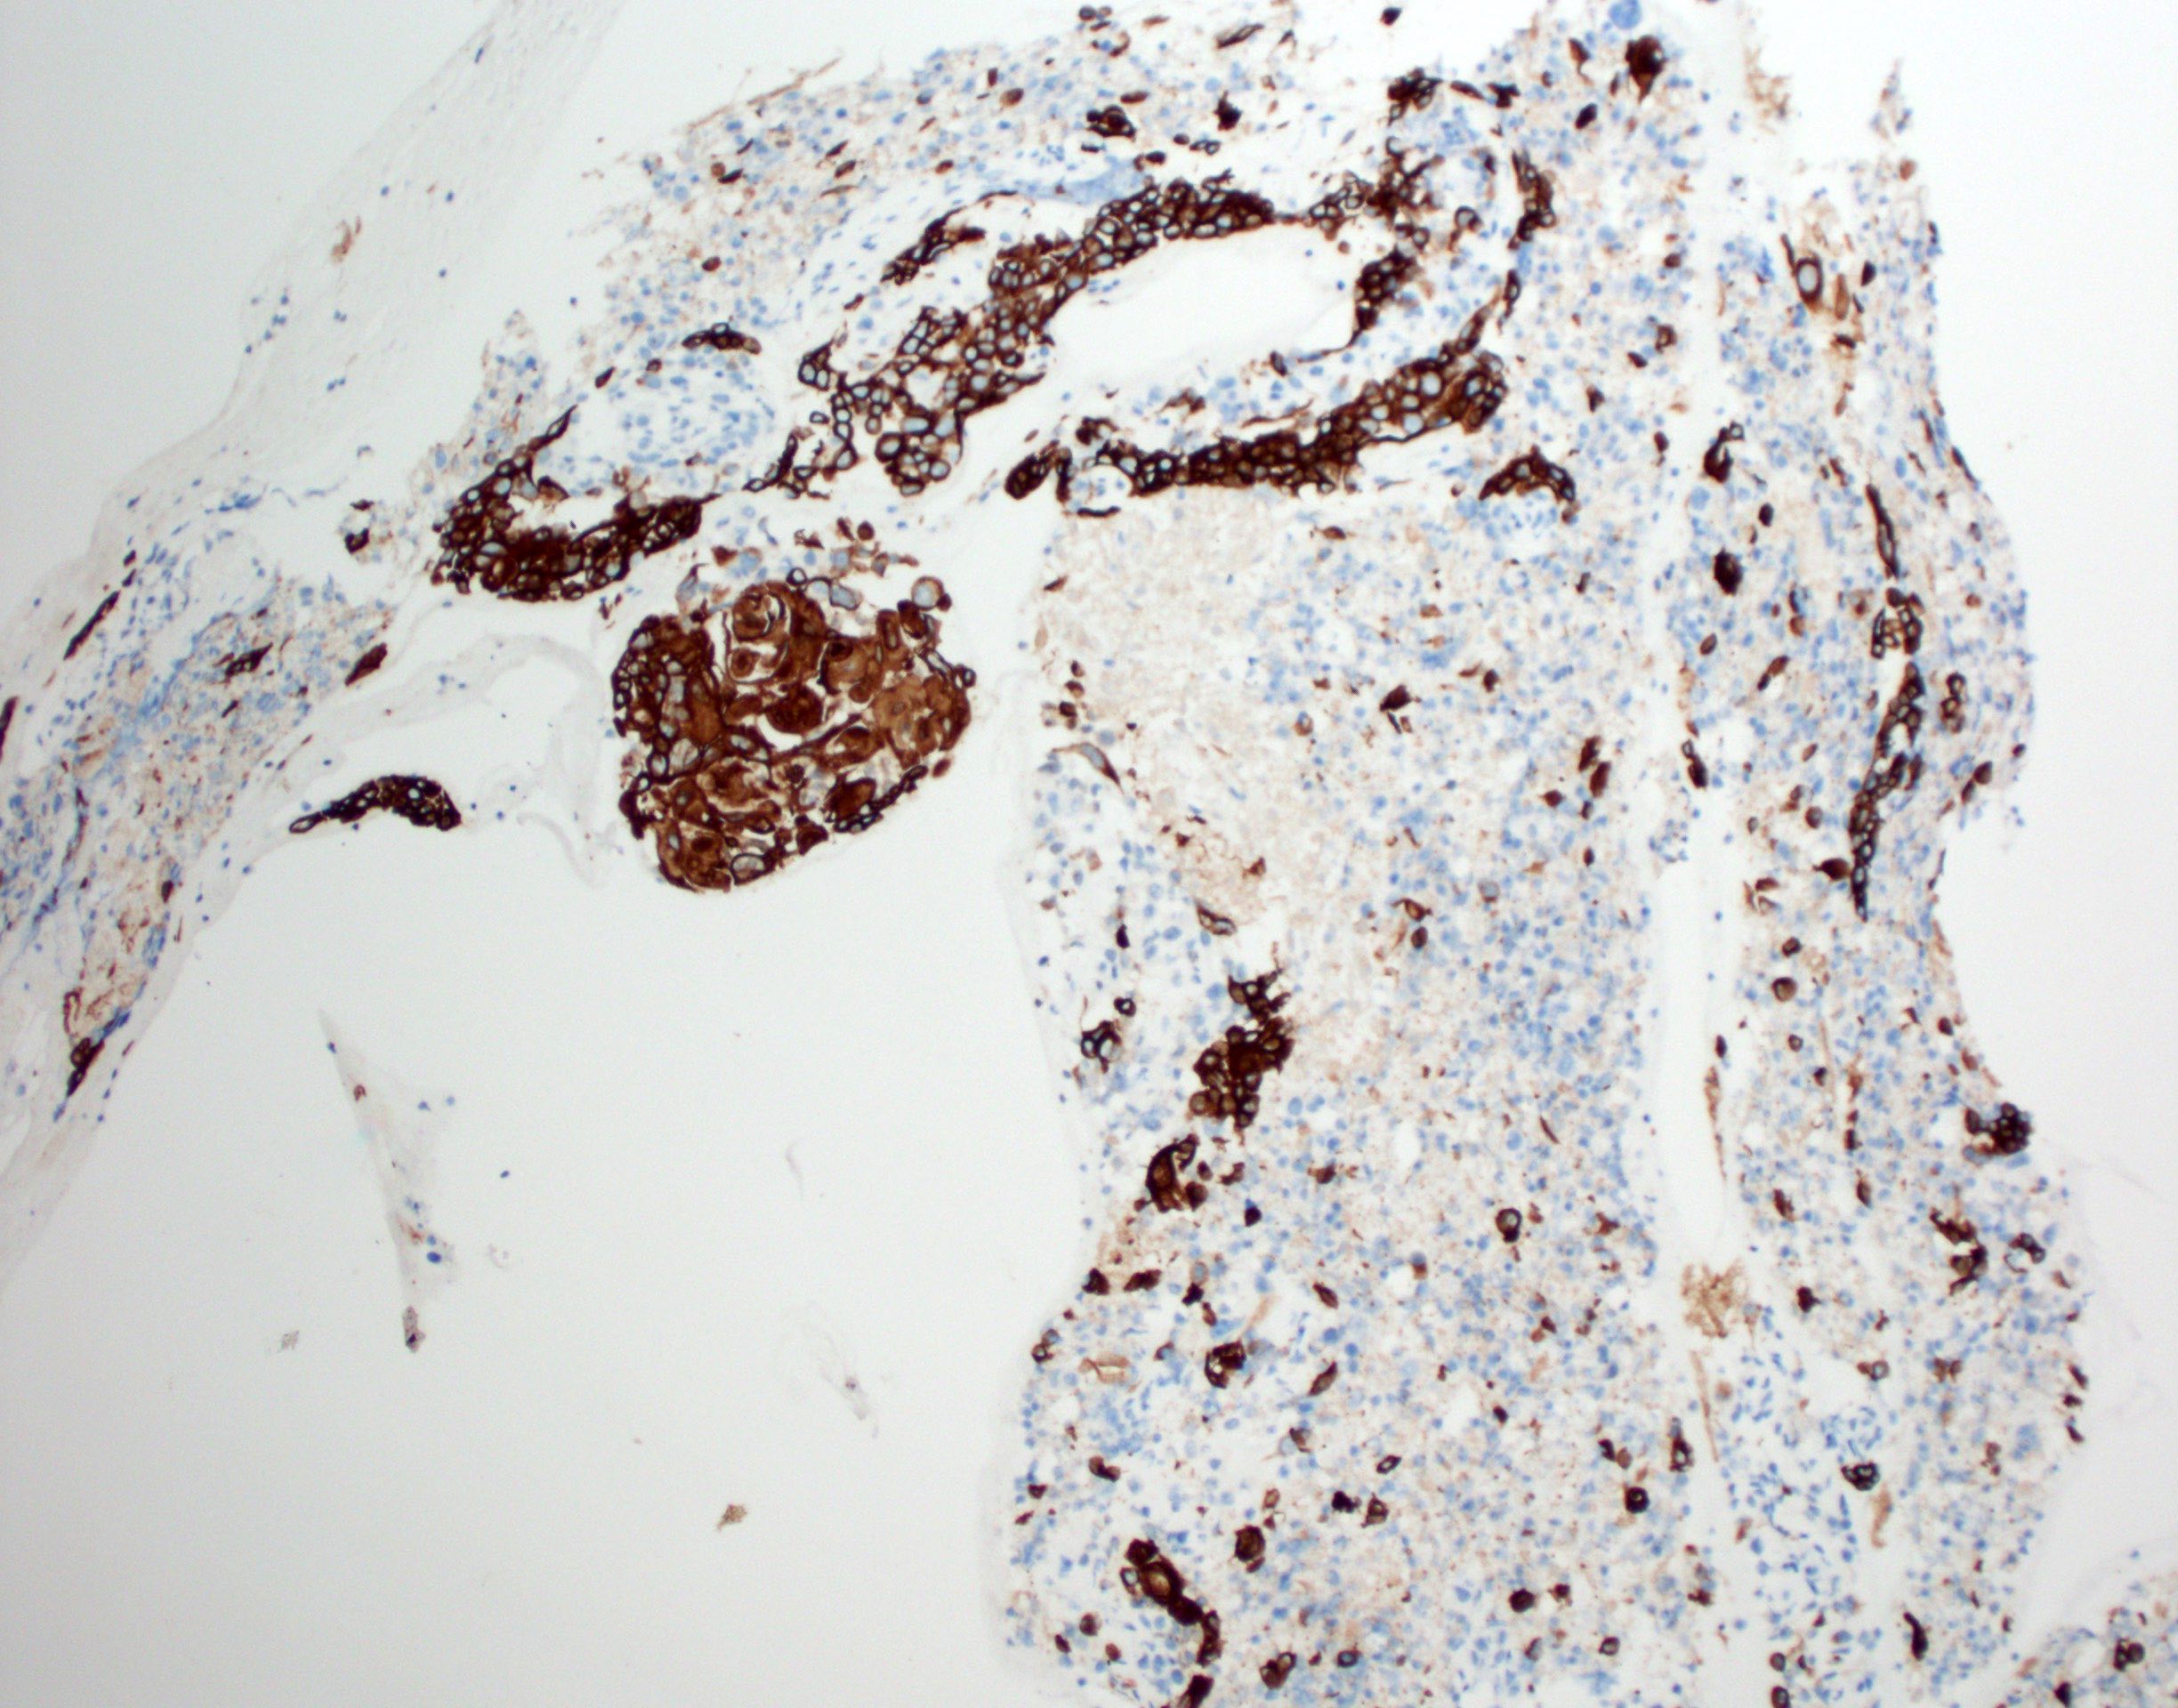

Microscopic (histologic) images

Contributed by Ruta Gupta, M.B.B.S., M.D.

Positive stains

- Diffusely and strongly positive: